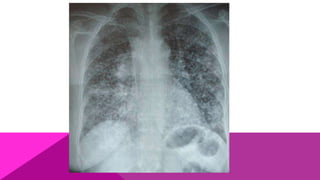

HISTOPLASMOSIS PRIMARIA

LEVE

Simula a una gripe banal, por lo que el ataque al estado

general es mínimo; la sintomatología está caracterizada

por fiebre moderada e irregular, cefalea, mialgias, astenia

y adinamia. A los rayos X en muy contadas ocasiones se

observan lesiones micronodulares.

MODERADA

La sintomatología aumenta, simulando una

neumonía atípica; el cuadro respiratorio es más

evidente, con presencia de tos, estertores y

discreta disnea; el ataque al estado general viene

acompañado por fiebre moderada y constante,

cefalea, dolores musculares y óseos. A los rayos X

se observa aumento de volumen de los ganglios

hiliares.

GRAVE

Es bastante parecida a los casos de tuberculosis;

se presenta como un cuadro muy agudo,

caracterizado por abundante tos con expectoración

mucoide, hemoptisis, marcada disnea; estertores

crepitantes o subcrepitantes, sibilancias y ataque

al estado general, caracterizado por astenia,

cefalea intensa, fiebre aguda y diaforesis; algunos

casos pueden presentar diarrea, que junto con la

alta temperatura se confunde fácilmente con fiebre

tifoidea.

HISTOPLASMOSIS PRIMARIA LEVE Simula auna gripe banal, por lo que el ataque al estado general es mínimo; la sintomatología está caracterizada por fiebre moderada e irregular, cefalea, mialgias, astenia y adinamia. A los rayos X en muy contadas ocasiones se observan lesiones micronodulares.

MODERADA La sintomatología aumenta,simulando una neumonía atípica; el cuadro respiratorio es más evidente, con presencia de tos, estertores y discreta disnea; el ataque al estado general viene acompañado por fiebre moderada y constante, cefalea, dolores musculares y óseos. A los rayos X se observa aumento de volumen de los ganglios hiliares.

GRAVE Es bastante parecidaa los casos de tuberculosis; se presenta como un cuadro muy agudo, caracterizado por abundante tos con expectoración mucoide, hemoptisis, marcada disnea; estertores crepitantes o subcrepitantes, sibilancias y ataque al estado general, caracterizado por astenia, cefalea intensa, fiebre aguda y diaforesis; algunos casos pueden presentar diarrea, que junto con la alta temperatura se confunde fácilmente con fiebre tifoidea.